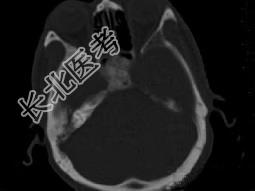

- 单项选择题男性,56岁, 鼻咽癌放疗后复查,CT扫描如图所示, 请选择正确的答案 ( )

D、放疗后骨炎